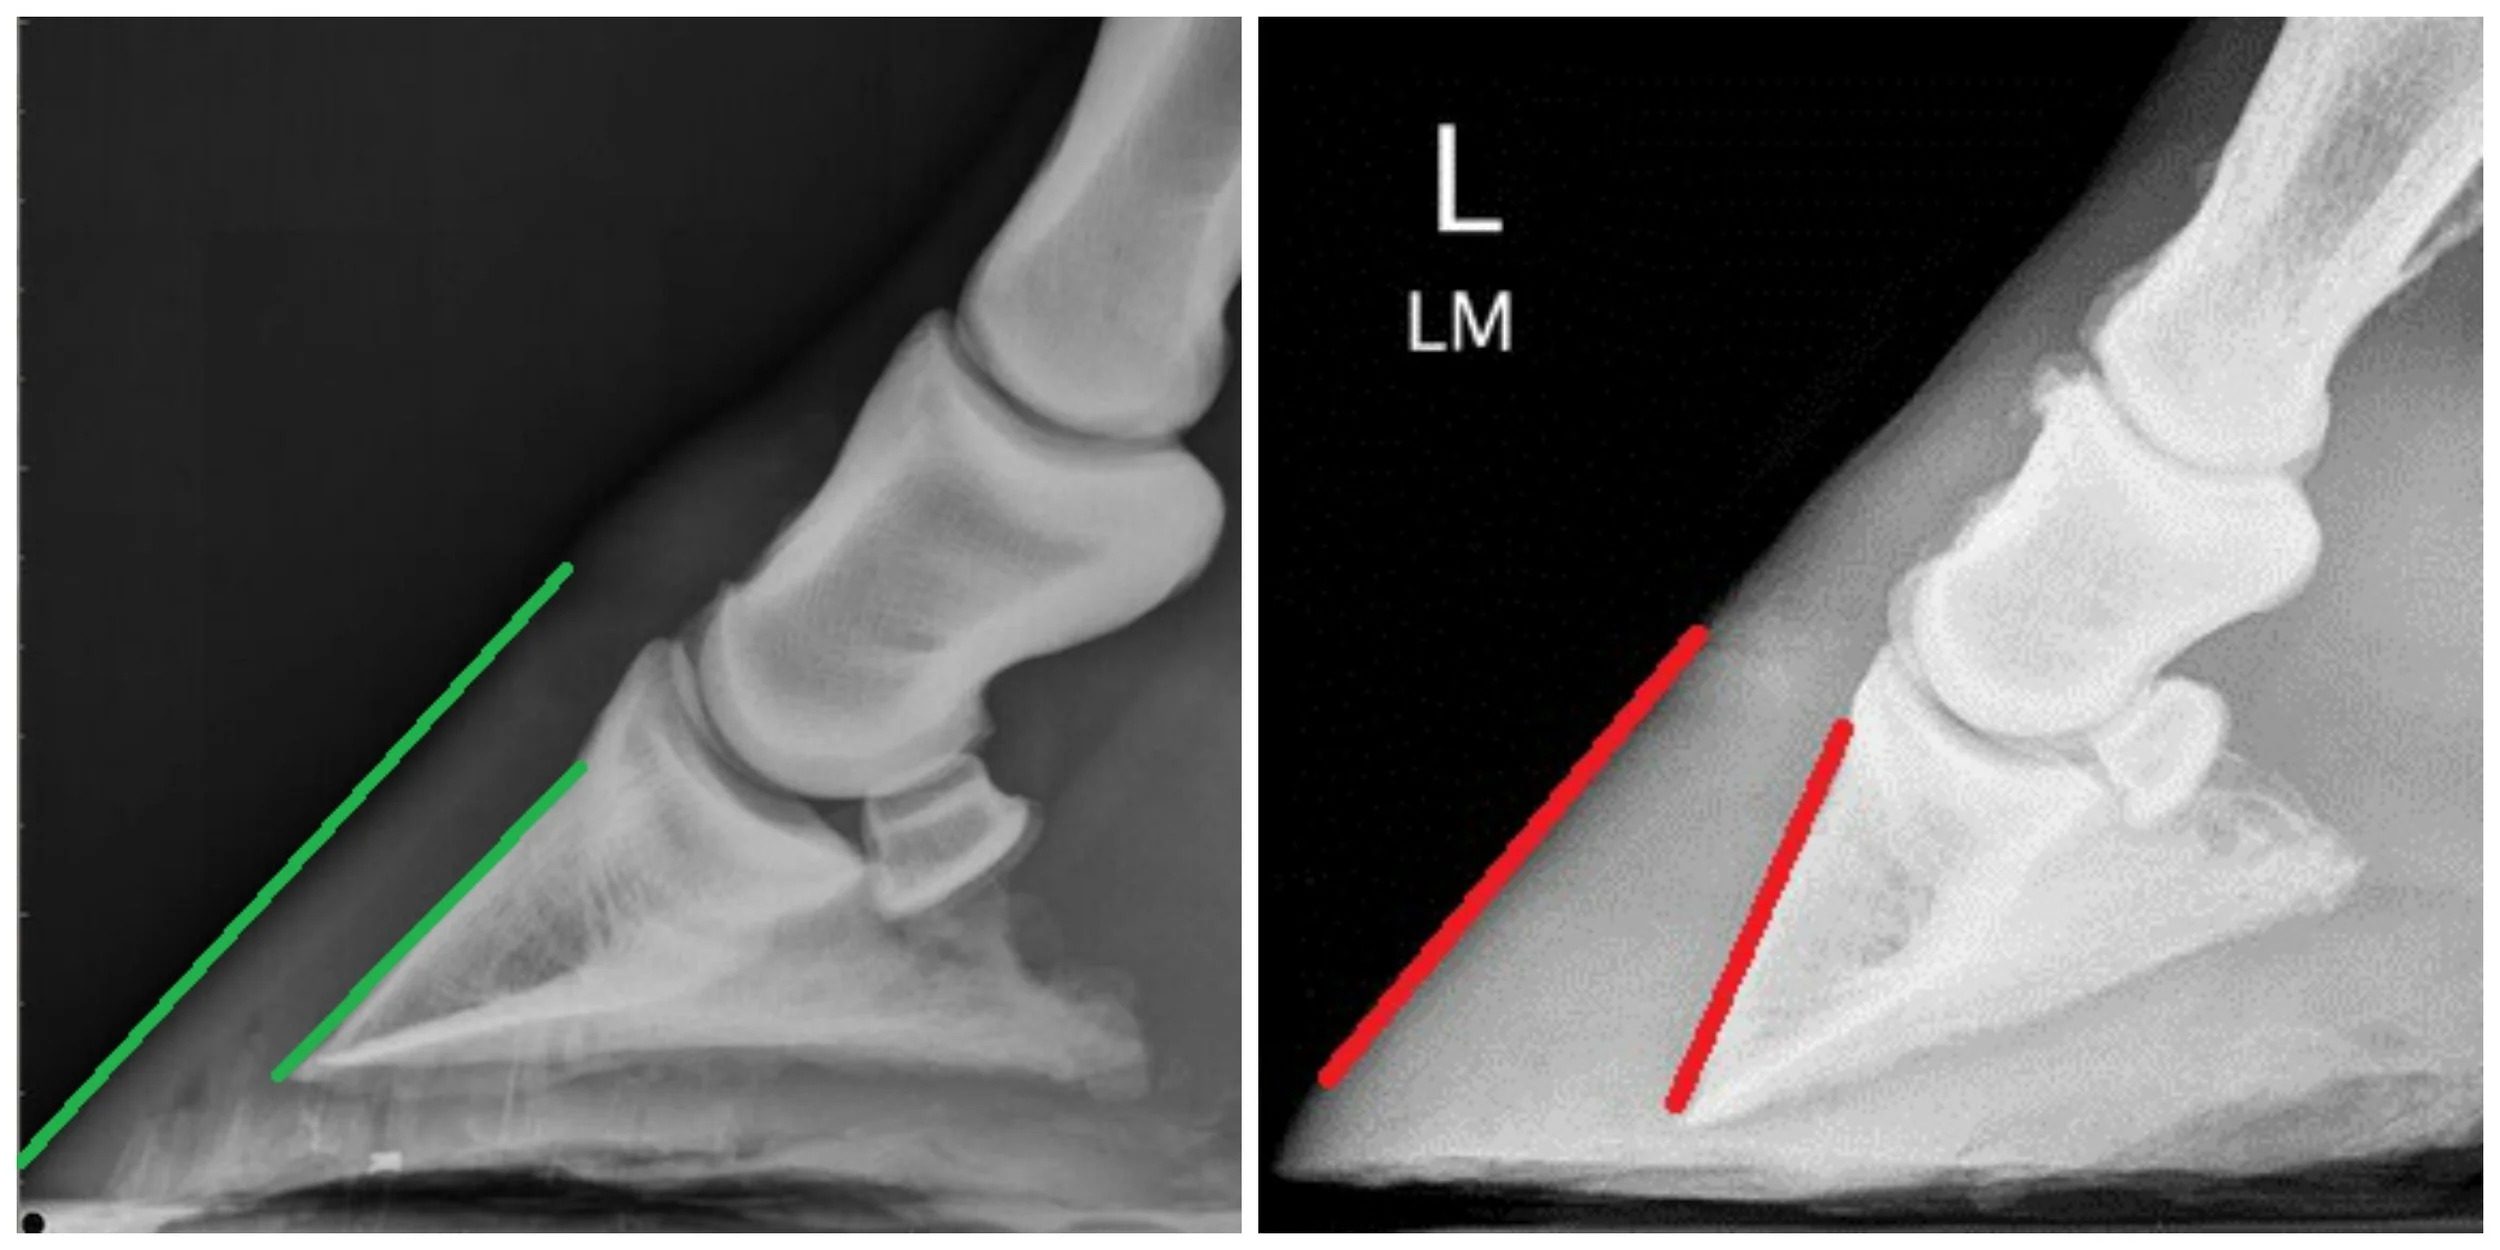

Founder is the inflammation of the laminae, the sensitive structures inside a horse’s hoof that attach the hoof wall to the pedal bone. When these laminae become inflamed, it can cause severe pain and structural damage, sometimes leading to the rotation or sinking of the pedal bone.